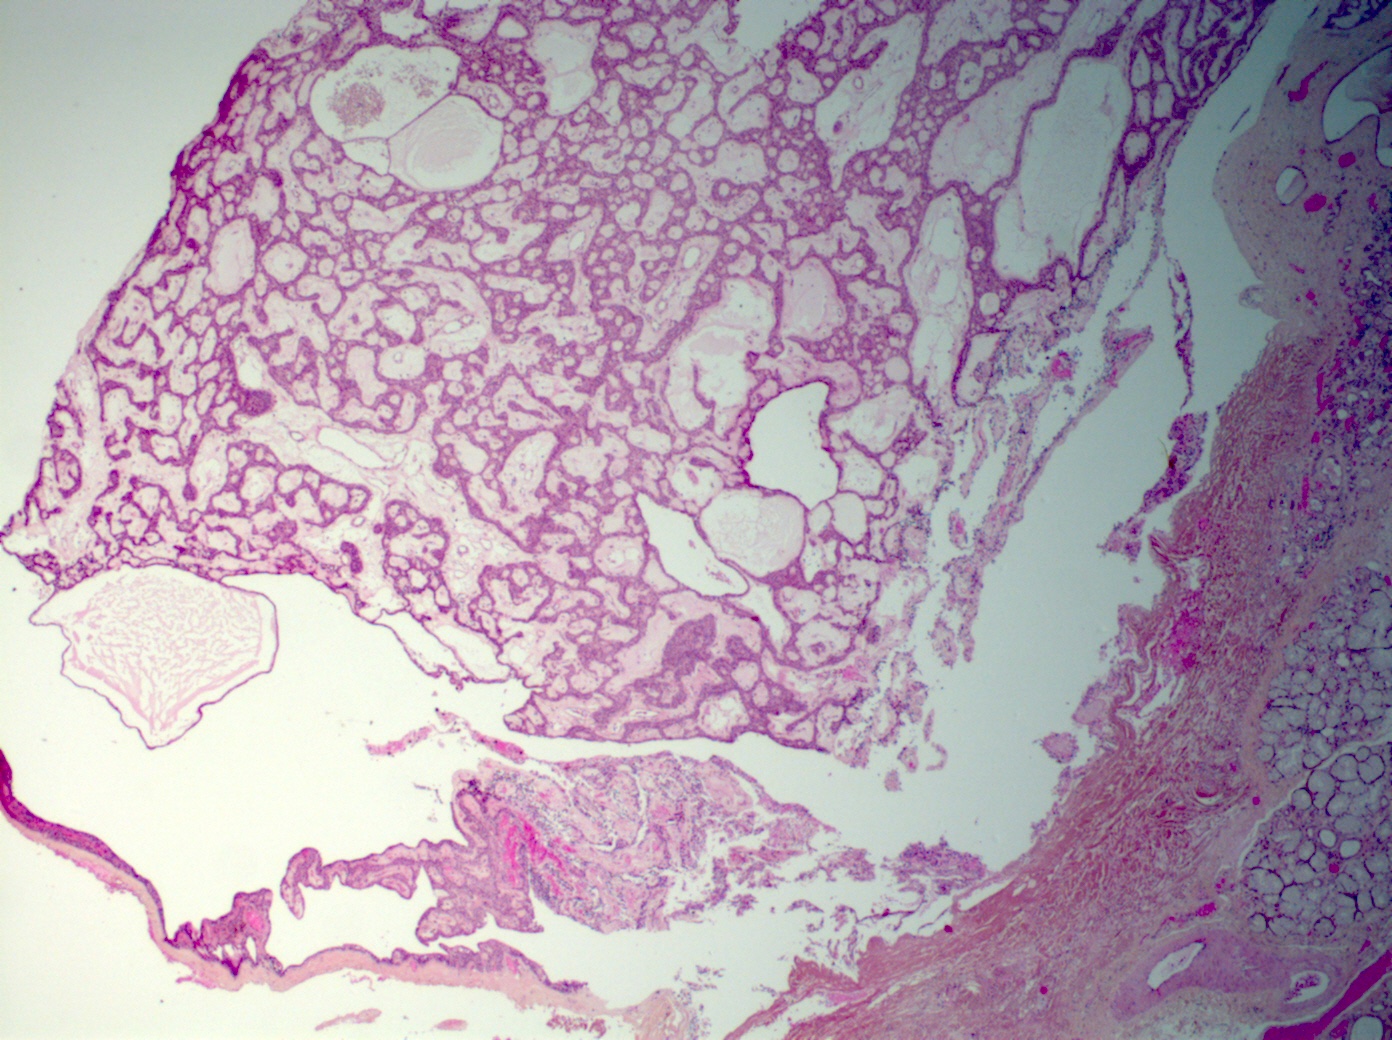

Microscopic (histologic) description

- Tumors may be single or multifocal

- Bilayered strands or ribbons or anastomosing cords or branching tubules

- Canalicular to cystic spaces between the cell strands; trabecular features

- Lack of an outer layer of myoepithelial cells

- Beading pattern, club ended cords

- May infiltrate capsule and show extracapsular tumor islands (including in the normal salivary gland / multiple tumors)

- Often cystic change

- Tumoral columnar or cuboidal cells, foci of basaloid cells

- Amphophil to eosinophilic cytoplasm, apocrine / oncocytic

- Round to elliptical, uniform nuclei, focally nucleoli, basophilic chromatin, rare to absent mitoses

- Mucous / mucinous metaplasia (Head Neck Pathol 2015;9:181)

- Pigmented cells

- Lacks or has exceptional necrosis (Head Neck Pathol 2015;9:181)

- Microliths, tyrosine crystals, morules and squamous balls (intraluminal) (J Craniomaxillofac Surg 2017;45:1754, Head Neck Pathol 2015;9:181, Histopathology 1999;35:502)

- Well vascularized, loose stroma; possibly sclerotic; perivascular eosinophil cuffs

- Luminal or stromal histiocytes (foamy, lipofuscin, hemosiderin), luminal hemorrhage, degenerated / infarcted stroma (Head Neck Pathol 2015;9:181)

- Malignant transformation not reported; lack of atypical figures (Head Neck Pathol 2015;9:181)

- Occasionally reported as collision tumors or hybrid tumors (Eur J Cancer B Oral Oncol 1996;32B:251)

Microscopic (histologic) images